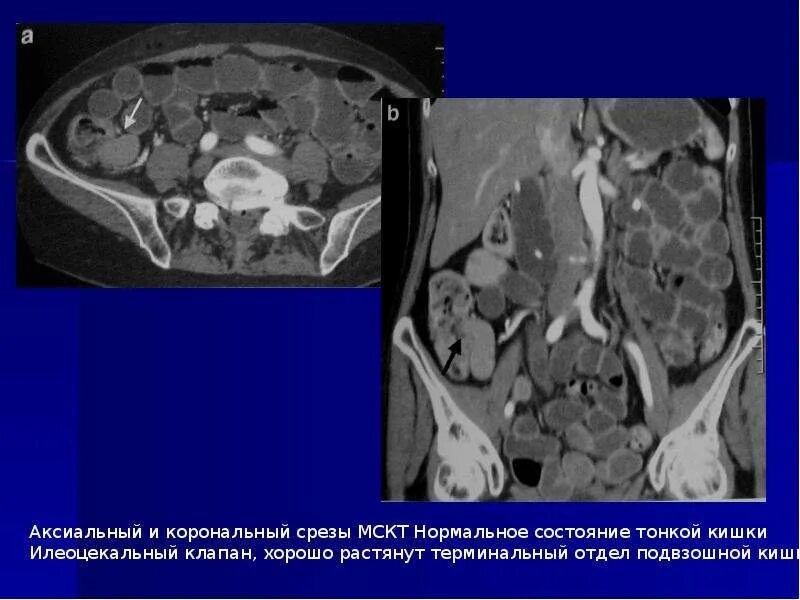

Диагностический срез